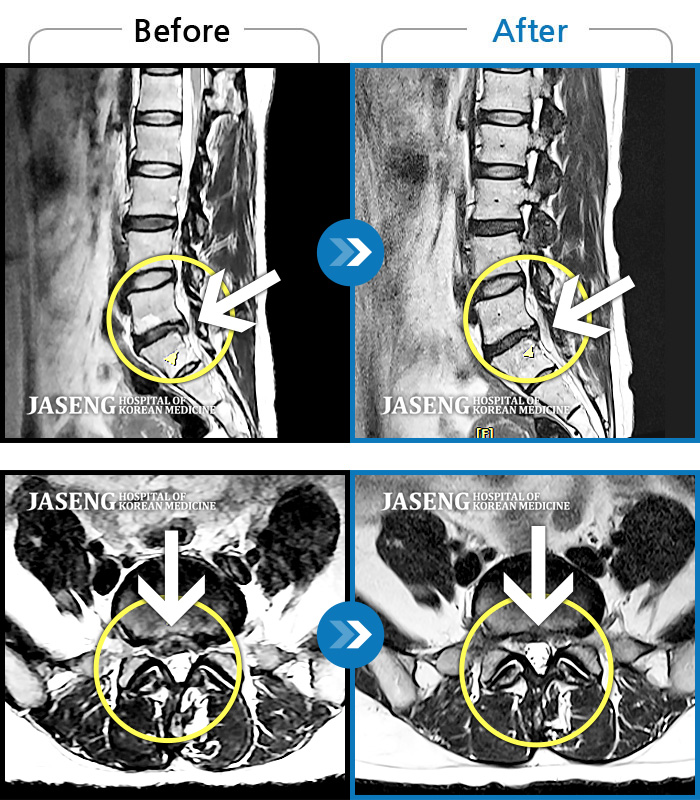

허리디스크

광주 · 이일석 원장

양측 허리부터 골반까지 묵직한 통증, 우측 다리 방사통이 심하여 내원하셨습니다.

촬영시기

2023.05.26 ~ 2025.08.16

2025.08.22